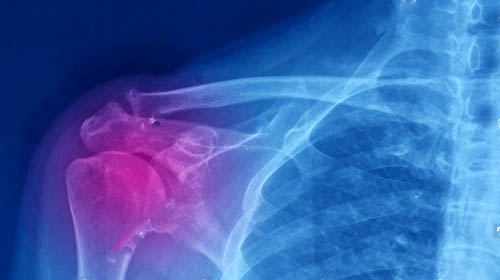

x-ray of shoulder area indicating joint pain